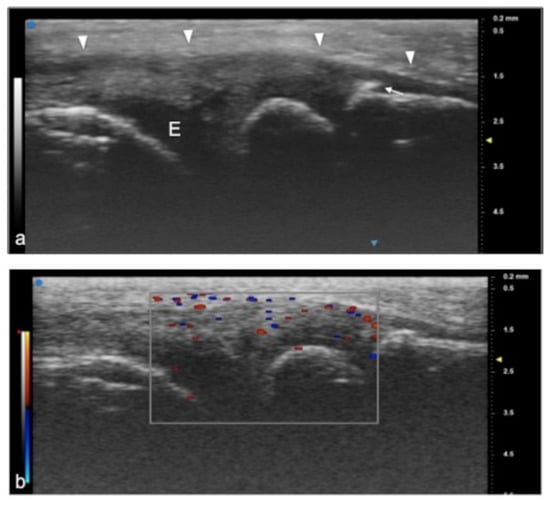

Figure 5.

Juvenile idiopathic arthritis. UHFUS gives clear details of pathological findings in pediatric patients with JIA. In (a), articular effusion (E) at the level of wrist and enthesophyte (white arrow). Thickened capsule (arrowheads) in (a) presenting with an increased Doppler signal (white square) in (b).